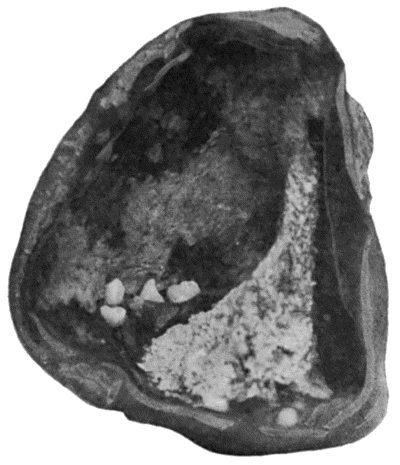

| 120. | Segment of Tibia resected for Brodie's Abscess | 449 |

| 121. | Radiogram of Brodie's Abscess in Lower End of Tibia | 451 |